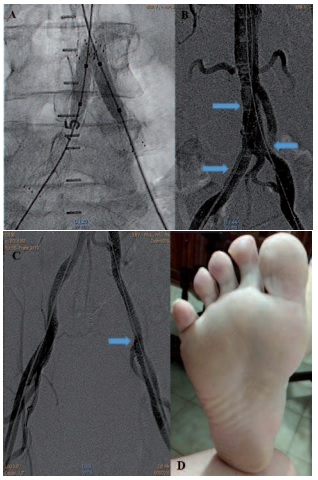

El síndrome del dedo azul como expresión de enfermedad aterosclerótica grave